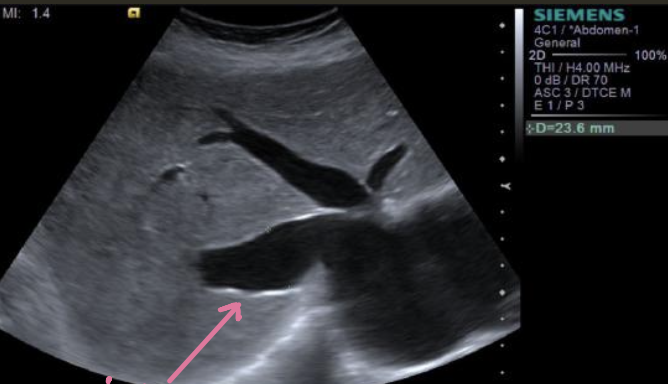

AAA (Abdominal Aortic Aneurysm) → focal dilation of aorta

2D US presentation: focally dilated AO (3 cm or greater), mural hypoechoic thrombus, wall calcifications, usually located infrarenal, can be fusiform or saccular

color doppler: turbulent helical flow

DDX: aortic dissection (aorta may be enlarged, but has intimal flap), pseudoaneurysm (focal outpouching w/ narrow neck, but not all 3 layers involved)